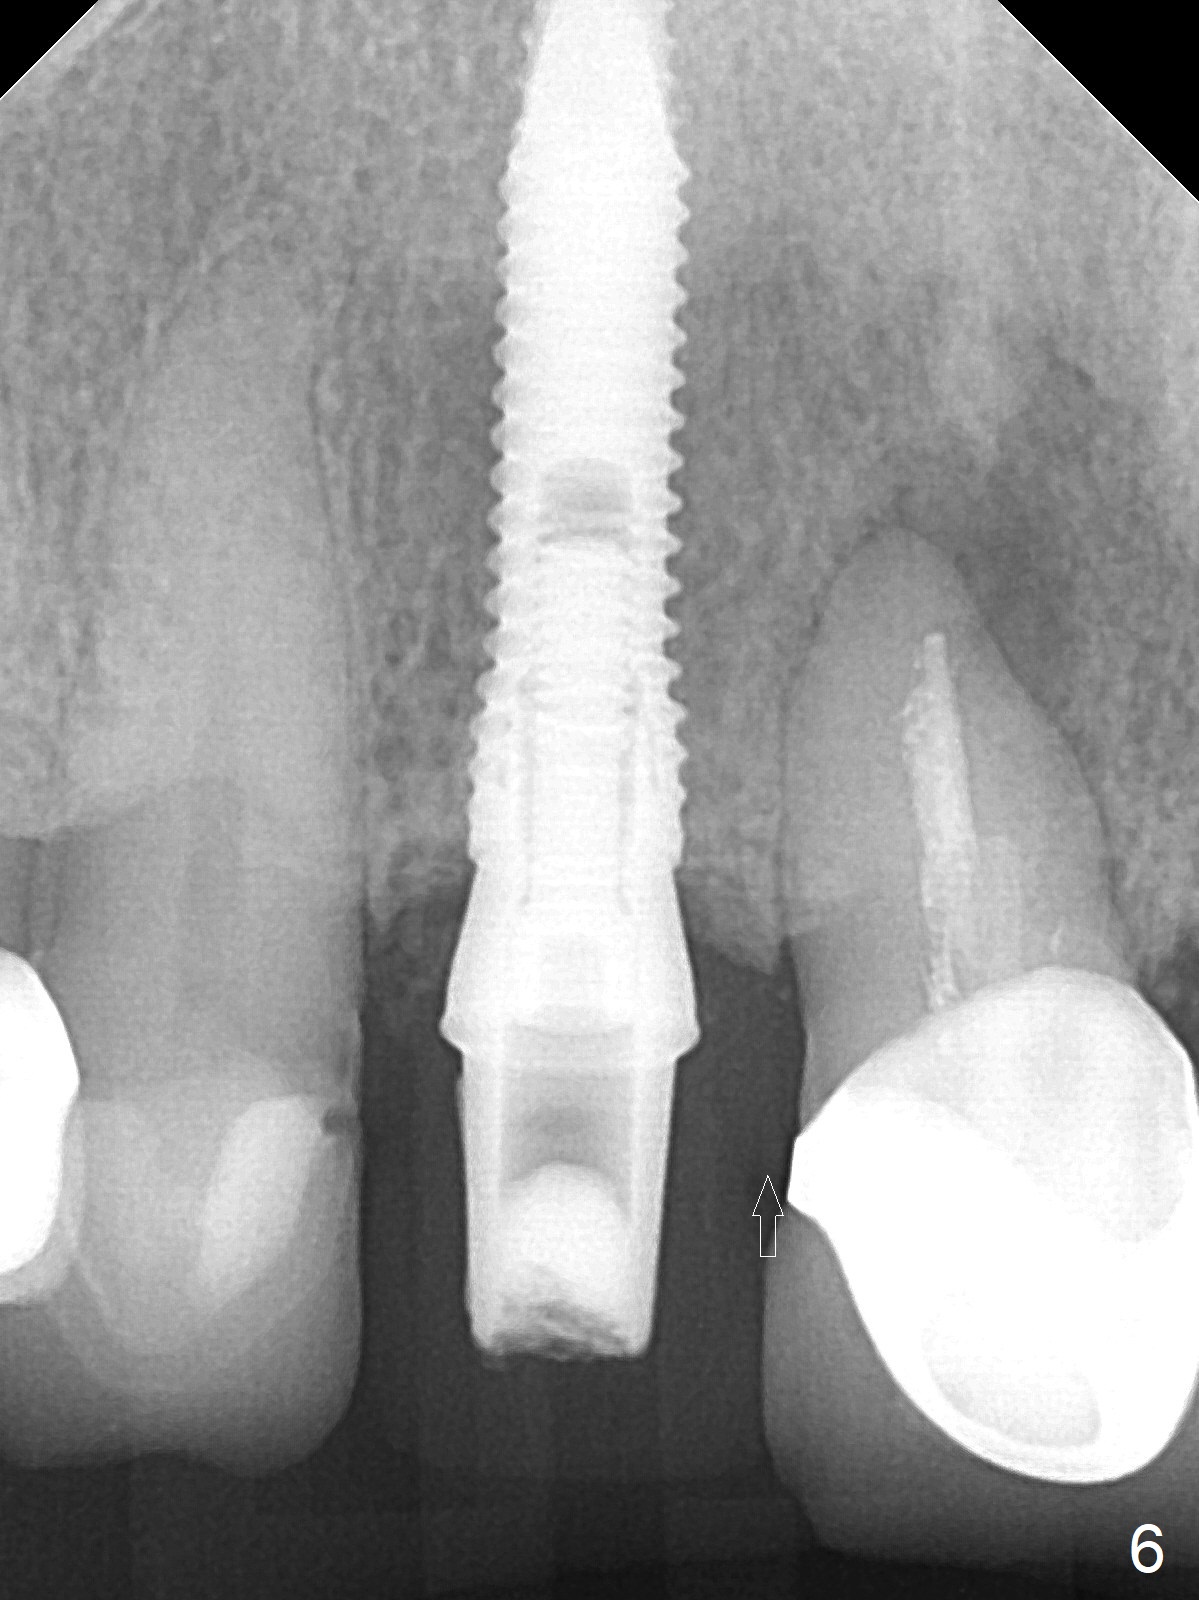

She returns for impression 4 months postop; the abutment margin is substantially subgingival (Fig.6 arrow). The abutment is changed to 4.5x4(4) mm one before impression. There is no bone resorption 9 months post cementation (Fig.7).